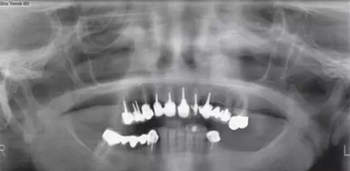

患者65歲,女性,非吸煙者,全身狀況欠佳,希望重獲咀嚼能力?;颊呶盖谐蟪霈F(xiàn)惡病質(zhì),消化功能受損,從而導(dǎo)致口腔狀況加重(圖1)。

圖1

患者3區(qū)磨牙缺失,#26冠修復(fù),頜曲線已改變。#13~15松動(dòng)3度(Lindhe和Muehlmanm分度)。牙根齲壞并根折,#14、15牙齦炎癥明顯但沒(méi)有膿腫和上頜竇炎。#47伸長(zhǎng),#47~43固定橋頜曲線異常。并沒(méi)有足夠的頜間距離能夠使#16作為拮抗。